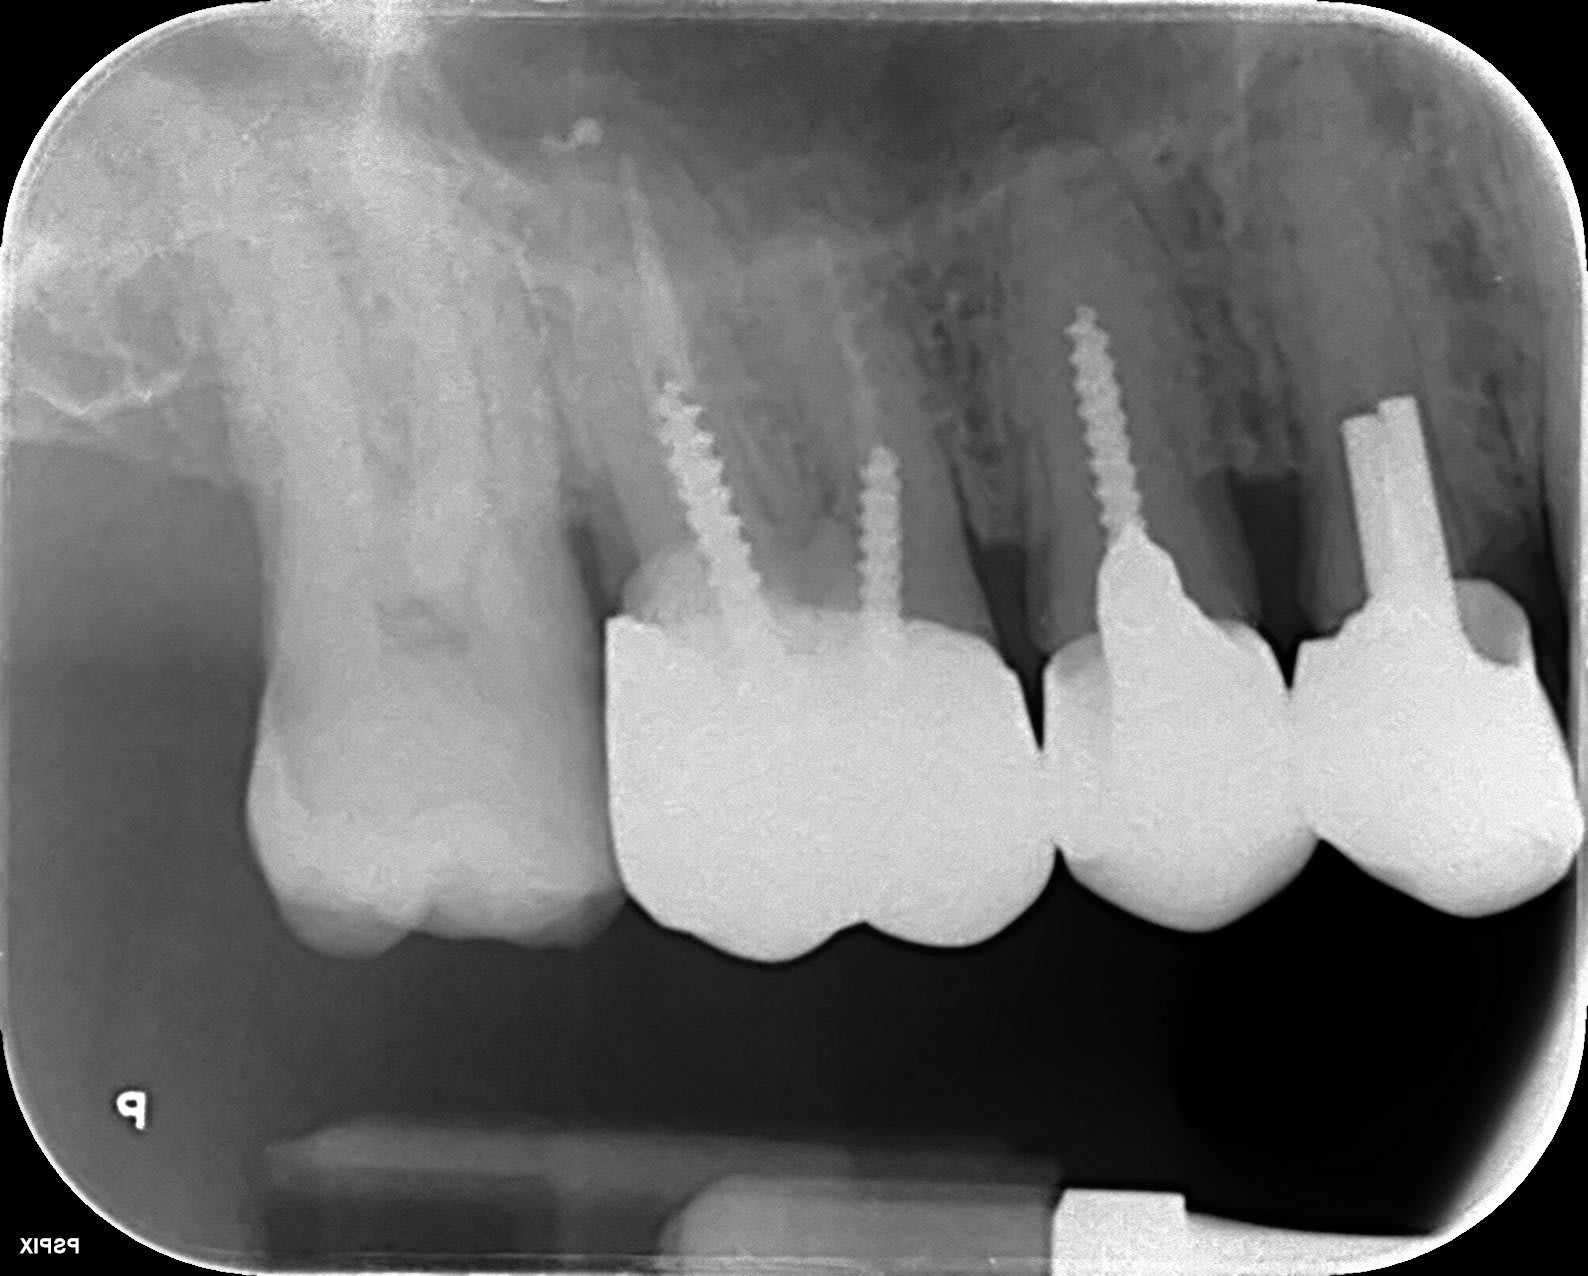

Heu, y aurait pas un petit quelque chose aussi sur la racine médiale de 26, comme qui dirait un MV2 oublié. Sinon de l’avis d’enlaye, vu l’évolution pulpaire de cette dent, pourquoi ne pas programmer une endo en sécurité, sous digue . Ca éclaircirai les choses. Bien souvent dans ma pratique une douleur bien localisée sur une dent apparement saine, c’est une fracture liée soit à une chute(parfois anodine) avec l’effet marteau de porte de la mandibule , soit a du clenching nocturne en porte à faux.

mon boss n'est pas chaud pour une endo sur la 36 car pour lui elle n'a rien....mais je peux peut être insister..car j'avoue être démoralisée (voire en déprime) par cette sensation de brulure....brulure plus autour de la 37 d'ailleurs

par contre c'est sur la 36 ou j'ai parfois mal quand je mange dessus.

CARIDENT.....si j'avais un LIPOE cela se verrait quand même sur la radio..car je n'ai pas l'impression que cela a changé depuis 2016 (voir historique de mes rétro).

Mais OUI un cone beam est peut être intéressant.

Un LIPOE peut passer complétement inaperçu sur une rétro, surtout au niveau des molaires mandibulaires à cause de l’inclinaison des dents. Suivant l'orientation du générateur et du capteur, la superposition des structure sur un cliché 2D peut masquer ce que l'on cherche à voir...